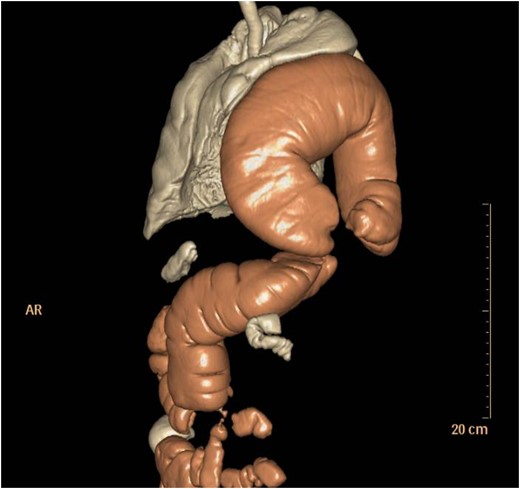

Thoraco-abdominal computed tomography (CT) showed the herniated bowel (transverse colon), translocated through a defect of about 7 cm in the left hemidiaphragm (Figs 2–4), a rightward deviation of the mediastinal structures and an atelectasis of the left lung (Fig. 5). The left colon had the appearance of a volvulus.

CT of chest showing defect on left side of the diaphragm and colon herniation in the thoracic cavity.

No signs of concern emerged from the follow-up for the neuroendocrine tumour until the last check, in particular no tumour recurrence was detected and there were no signs or symptoms of a diaphragmatic defect. During the follow-up a CT and ultrasonography (US) were performed, both with negative outcomes. The only post-operative issue was a pancreatic fistula that was conservatively treated and that spontaneously resolved some months later. The patient underwent explorative laparotomy, reduction of the left DH, resection of the necrotic transverse colon with direct stapled side-to-side colic anastomosis, diaphragmatic suture and thorax drainage (Figs 6 and 7). The diaphragmatic defect was repaired with interrupted suture. The recovery was complicated by ipsilateral pleural effusion and obstinate constipation, though the patient was discharged on the fourteenth post-operative day, apparently in good health. The post-operative course was uneventful. One month later a thoraco-abdominal CT scan was performed, with no signs of recurrent diaphragmatic hernia. The oncologic follow-up was negative and the patient is still alive and apparently in good health.